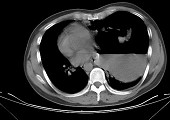

- 单项选择题女,6岁, 胸闷,咳嗽, 胸部CT如图,最可能的诊断为 ( )

A、畸胎瘤

B、右侧液气胸

C、右肺肺大疱

D、右侧脓胸

E、支气管囊肿并感染